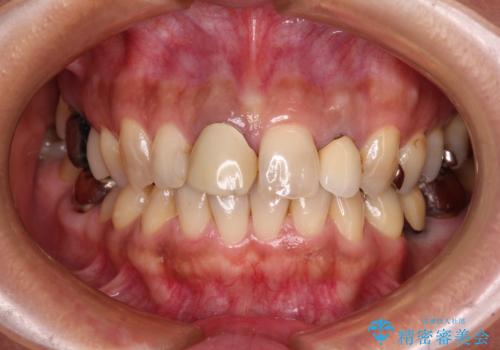

- 保険診療でのクラウンが変色してしまったとのことで来院された患者様です。

根管治療がされていなかったため、まずは根管治療を行い、その後オールセラミッククラウンにて補綴することとしました。

左上の歯も歯肉縁部分にメタルの色が見えており、合わせて治療することをお勧めしましたが、今回は1歯のみを治療することとしました。